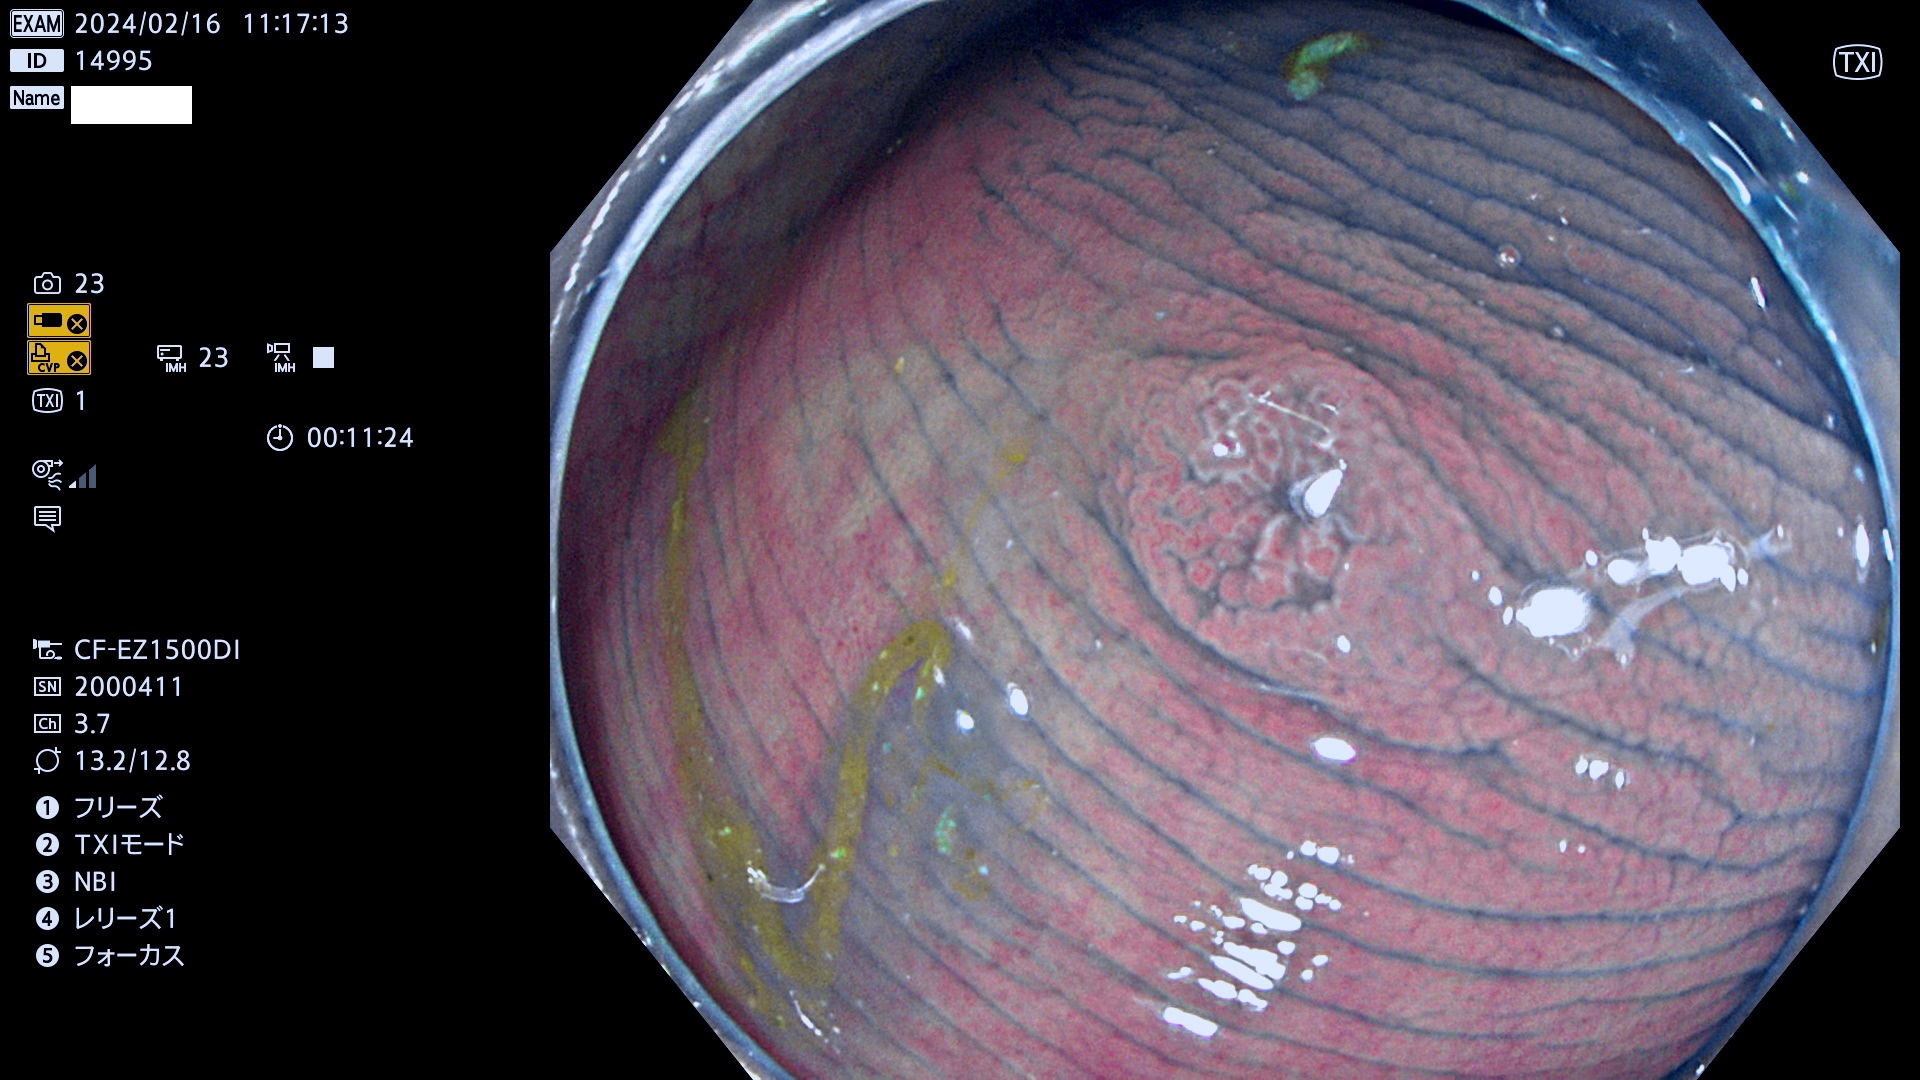

今週のUb、Uc型腺腫

表面型腺腫(Flat Adenoma)の中で、完全に平坦な物をUb、陥凹している物をUcと呼びます。平坦隆起型(Ua)よりも、発見が難しく危険な病変です。

毎週の検査(木・金・土・日)に発見されたUb、Uc型・腺腫を、その週の日曜の夜にUPし1週間、提示します。

抽出の対象期間 2024年2月15日(木)〜2月18(日)の4日間(40件の検査)10件 (10/40=25%)